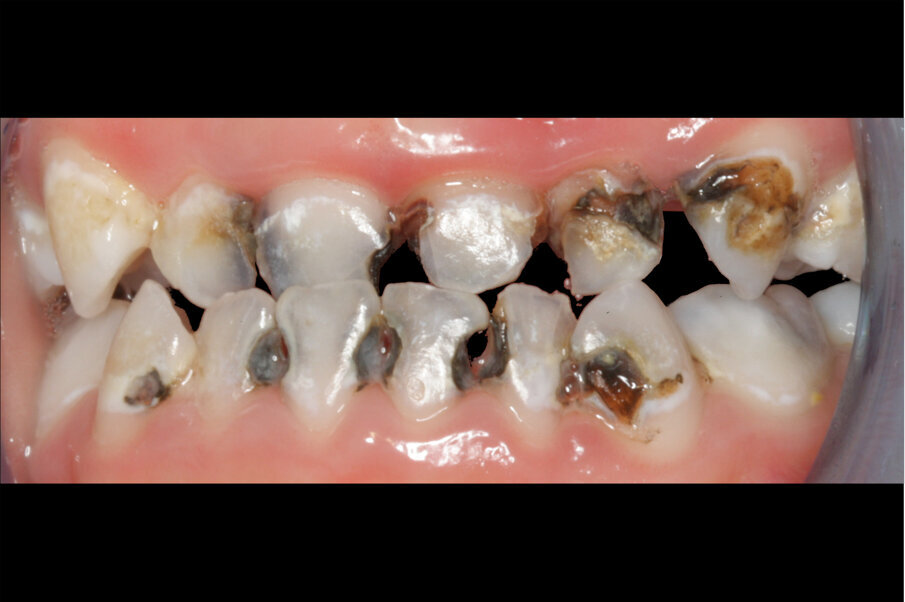

Afbeelding 3. Casus 2: 29-09-17. Eerste bezoek. Actieve cariës-instructies en ZDF aangebracht.

Afbeelding 4. Casus 2: 09-02-18. Tweede bezoek. Na 4 maanden klachtenvrij.